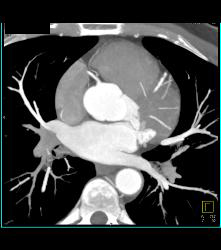

Normal Left Anterior Descending Coronary Artery (LAD)